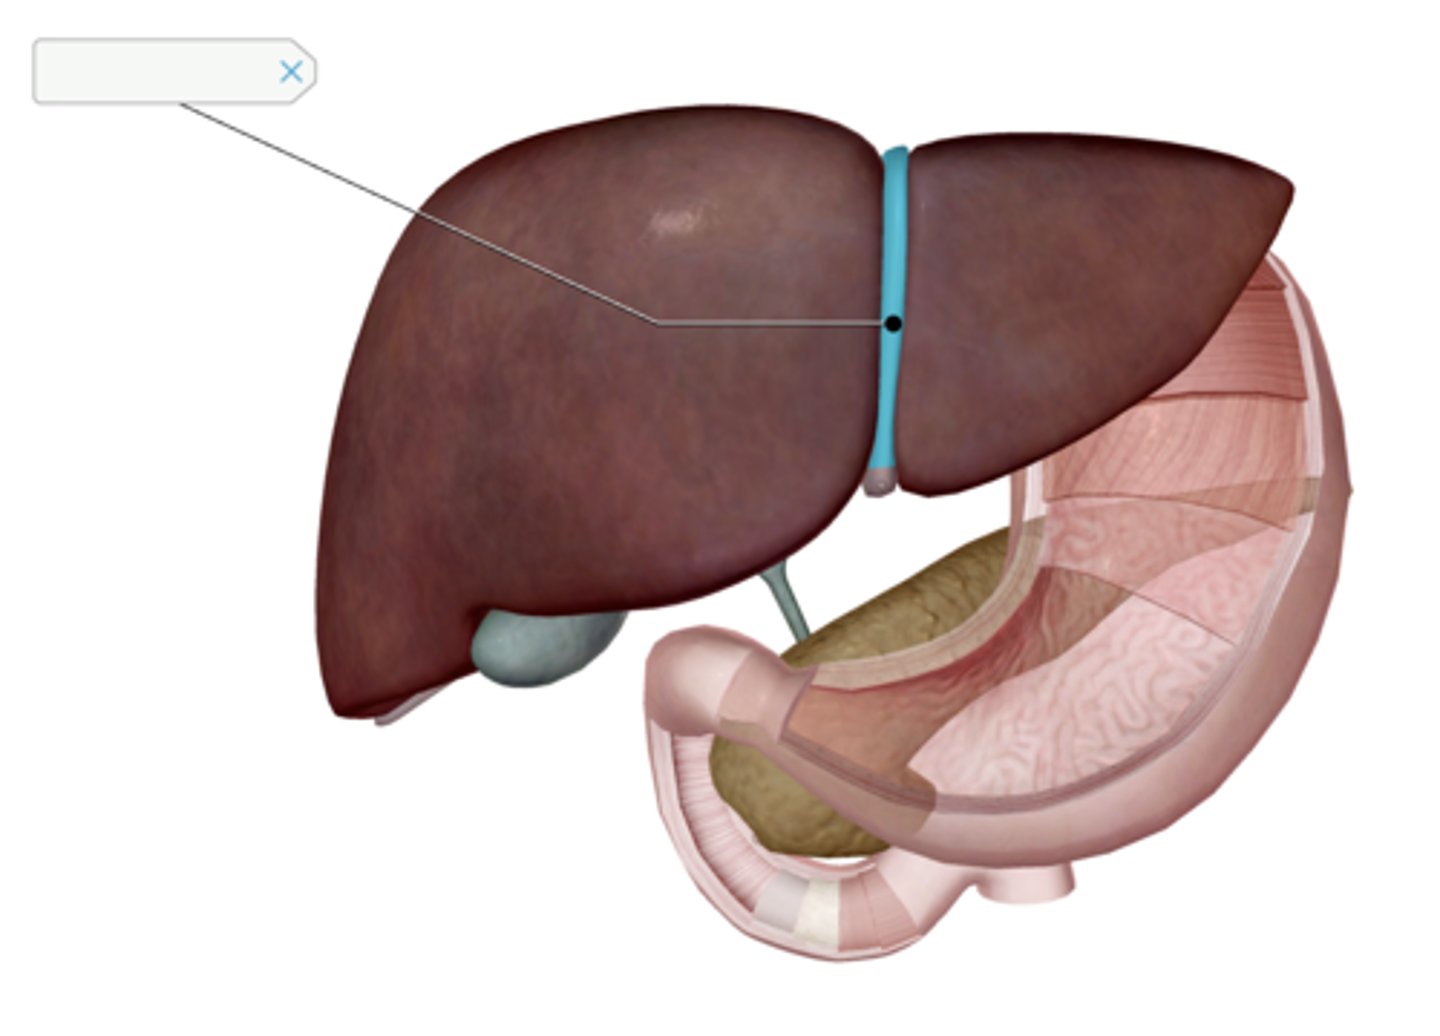

Pyloric sphincter

Gallbladder

Cystic duct

Common hepatic duct

Common bile duct

Pancreas

Main pancreatic duct (duct of Wirsung)

Liver

Falciform ligament

Duodenum

Duodenal papilla